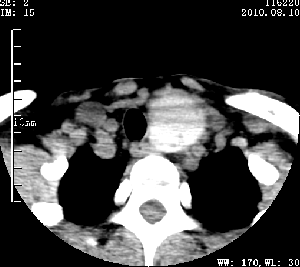

标题: CT28317:病人近几天无意间发现颈部肿块。 [打印本页]

标题: CT28317:病人近几天无意间发现颈部肿块。

甲状腺左叶局限性结节性甲状腺肿可能。建议增强扫描。

病变边界清楚,周围间隙清晰,甲状腺左叶(甲状旁腺?)肿大,右叶甲状腺腺瘤。

病变边界清楚,周围间隙清晰,左叶甲状腺肿大,右叶甲状腺小腺瘤。